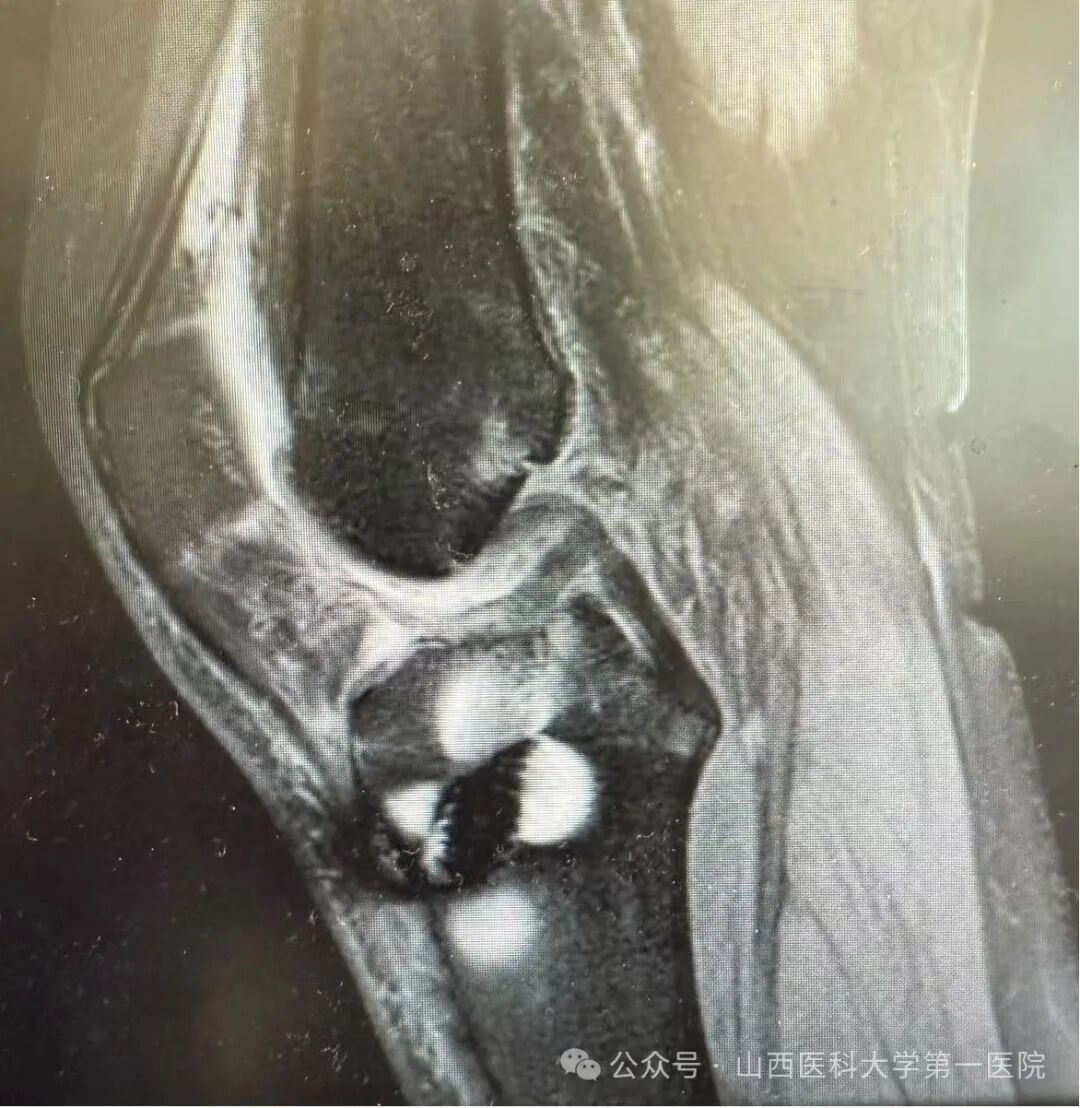

(术后MRI显示人工韧带重建前交叉韧带位置)与自体韧带不同的是,人工韧带是分段设计的聚酯材料,力学强度可达5500N,几乎是自体肌腱强度的3.2倍以上。它由两端编织与中间游离丝仿生旋转设计两部分组成,通过穿越ACL残端组织以诱导自体纤维组织与移植物游离丝整合,两端挤压螺钉固定,因此,人工韧带的优点即:手术创伤小、强度高、能早期重返运动,有研究显示人工韧带用于前交叉韧带的失败率要低于自体移植物。